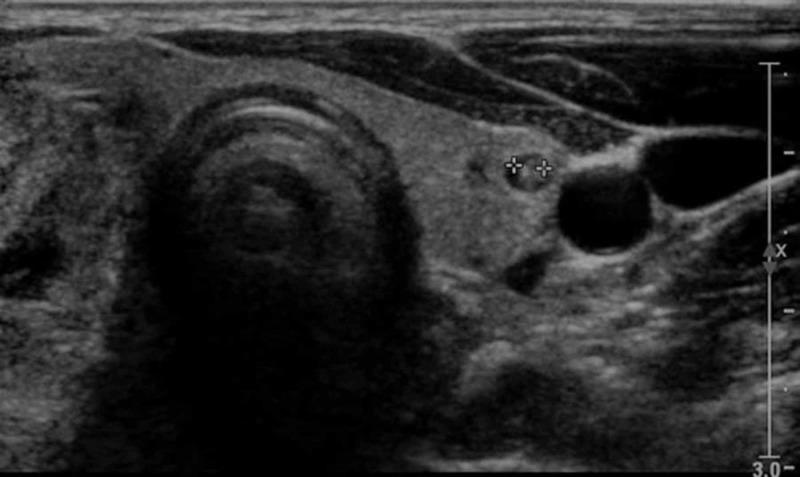

The presentation of atherosclerosis with concomitant hyperthyroidism is not uncommon. Hyperthyroidism predisposes to worse cardiovascular pathologies like systolic hypertension, atrial fibrillation, and hypercoagulability. Drug-eluting stents, on the other hand, have emerged as a miracle treatment choice for patients having atherogenic conditions. They have the highest success rates when it comes to minimizing in-stent restenosis (ISR) during short-term follow-up. There is scarce literature that assesses the correlation of multinodular goiter (MNG) to ISR, especially in Pakistan, and thus any probable association between the two is left untouched. We report a case of a 57-year-old female who is a known hyperthyroid with a massive MNG, presenting with worsening chest pain. She had undergone sirolimus-eluting stent (SES) implantation in left anterior descending artery (LAD) six months back. Cardiac catheterization confirmed restenosis of the SES in the LAD, along with the occlusion of left circumflex and right coronary artery, accompanied by grade I diastolic dysfunction and mild aortic regurgitation on echocardiography.

动脉粥样硬化合并甲状腺功能亢进的情况并不少见。甲状腺功能亢进易引发更严重的心血管疾病,如收缩期高血压、心房颤动和高凝状态。另一方面,药物洗脱支架已成为患有动脉粥样硬化疾病患者的一种神奇治疗选择。在短期随访中,它们在最小化支架内再狭窄(ISR)方面成功率最高。评估多结节性甲状腺肿(MNG)与ISR之间相关性的文献很少,尤其是在巴基斯坦,因此两者之间的任何可能关联都未得到探讨。我们报告一例57岁女性病例,她是一名已知的甲状腺功能亢进患者,患有巨大的MNG,出现胸痛加重症状。她六个月前在左前降支(LAD)植入了西罗莫司洗脱支架(SES)。心脏导管检查证实LAD处的SES再狭窄,同时左旋支和右冠状动脉闭塞,超声心动图显示伴有I级舒张功能障碍和轻度主动脉瓣反流。